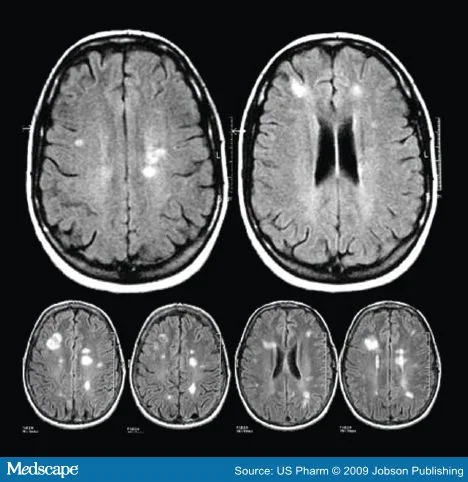

She shows me my MRI and explains that there are lesions on my brain that indicate I have Multiple Sclerosis (MS).

She's a bit perplexed though, because I had absolutely no bodily symptoms or family history, but the inflammation of my brain and the lesions present were

aggressive

.

My MRI looked something like this, with more lesions (the white spots) present and a ring of inflammation that showed white around the perimeter of my brain.